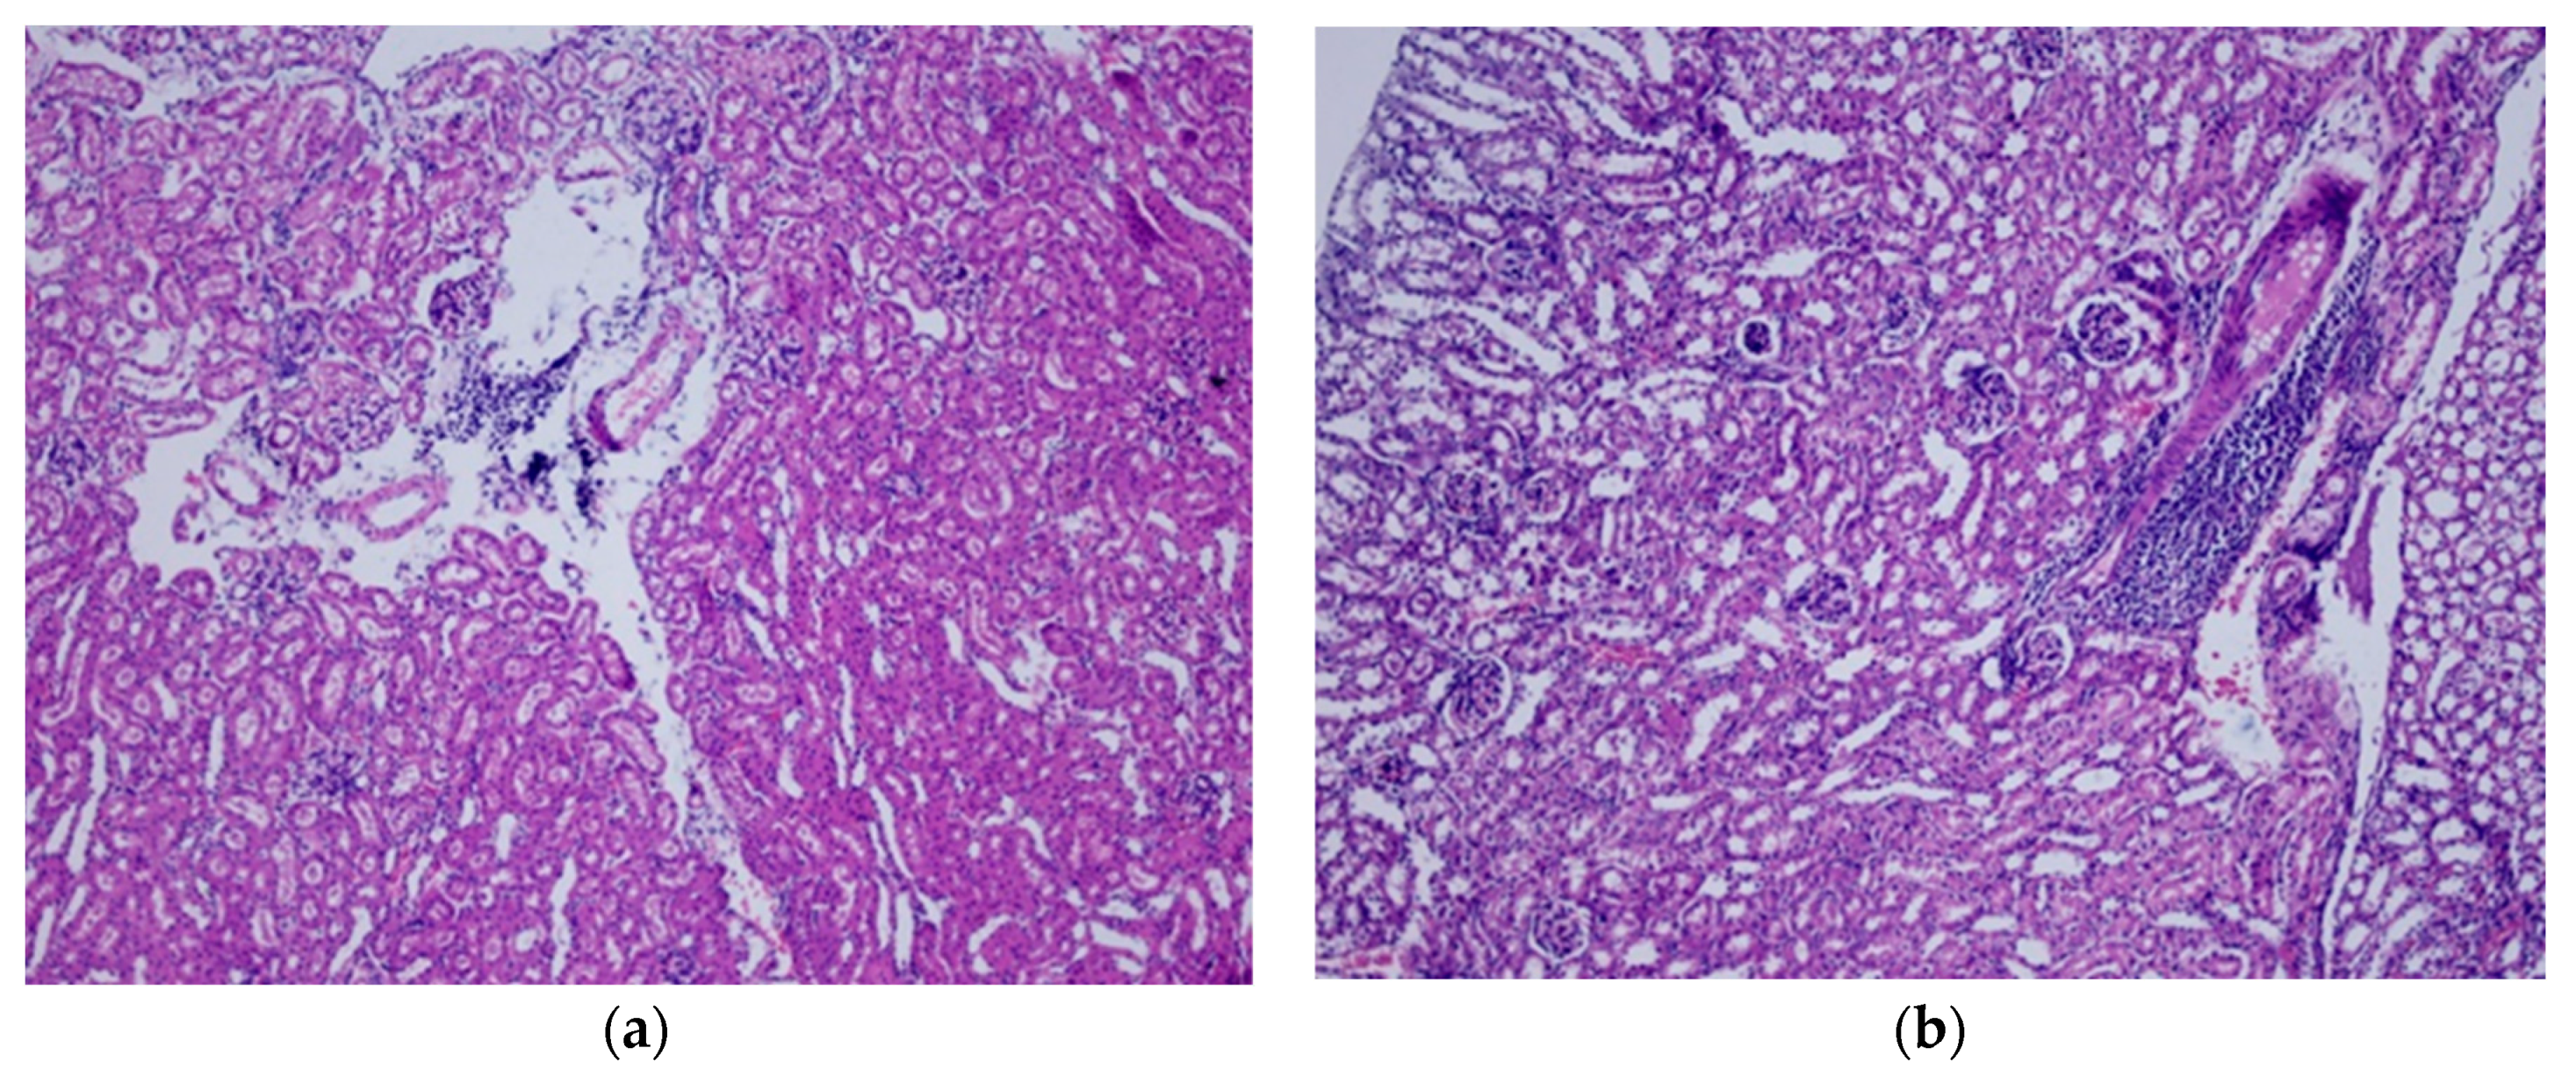

2.7. Histopathological Analysis

3.2. Repeated Dose Toxicity Study for 28 Days